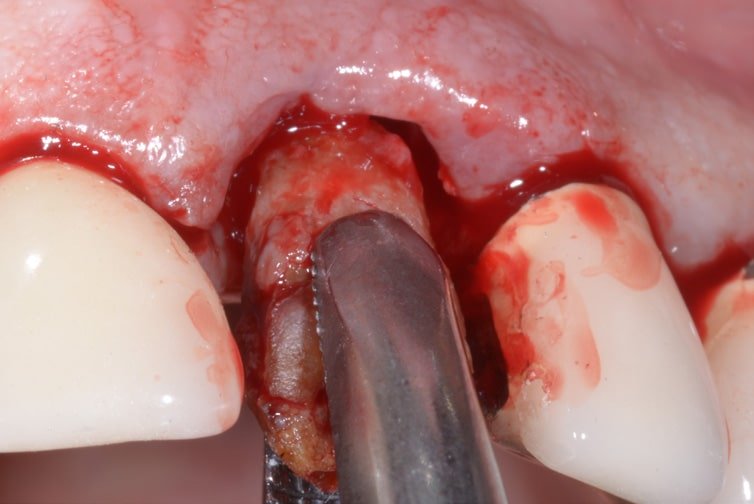

Extraction of a compromised central incisor, cleaning of the alveolus and insertion an EV line implant – self-tapping thread, under-prepared osteotomy – in the post-extraction phase for better maintenance of the bone volume.